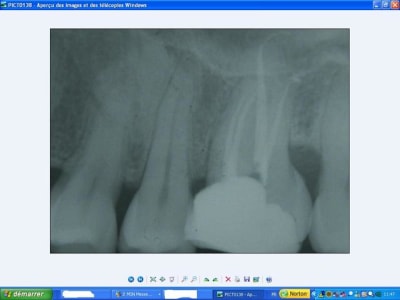

tiens ma belle alors pour me faire pardonner.

T'es vache avec les p'tits jeunes, purée! ;)

36préop ism6hn - Eugenol

36postop tmfern - Eugenol